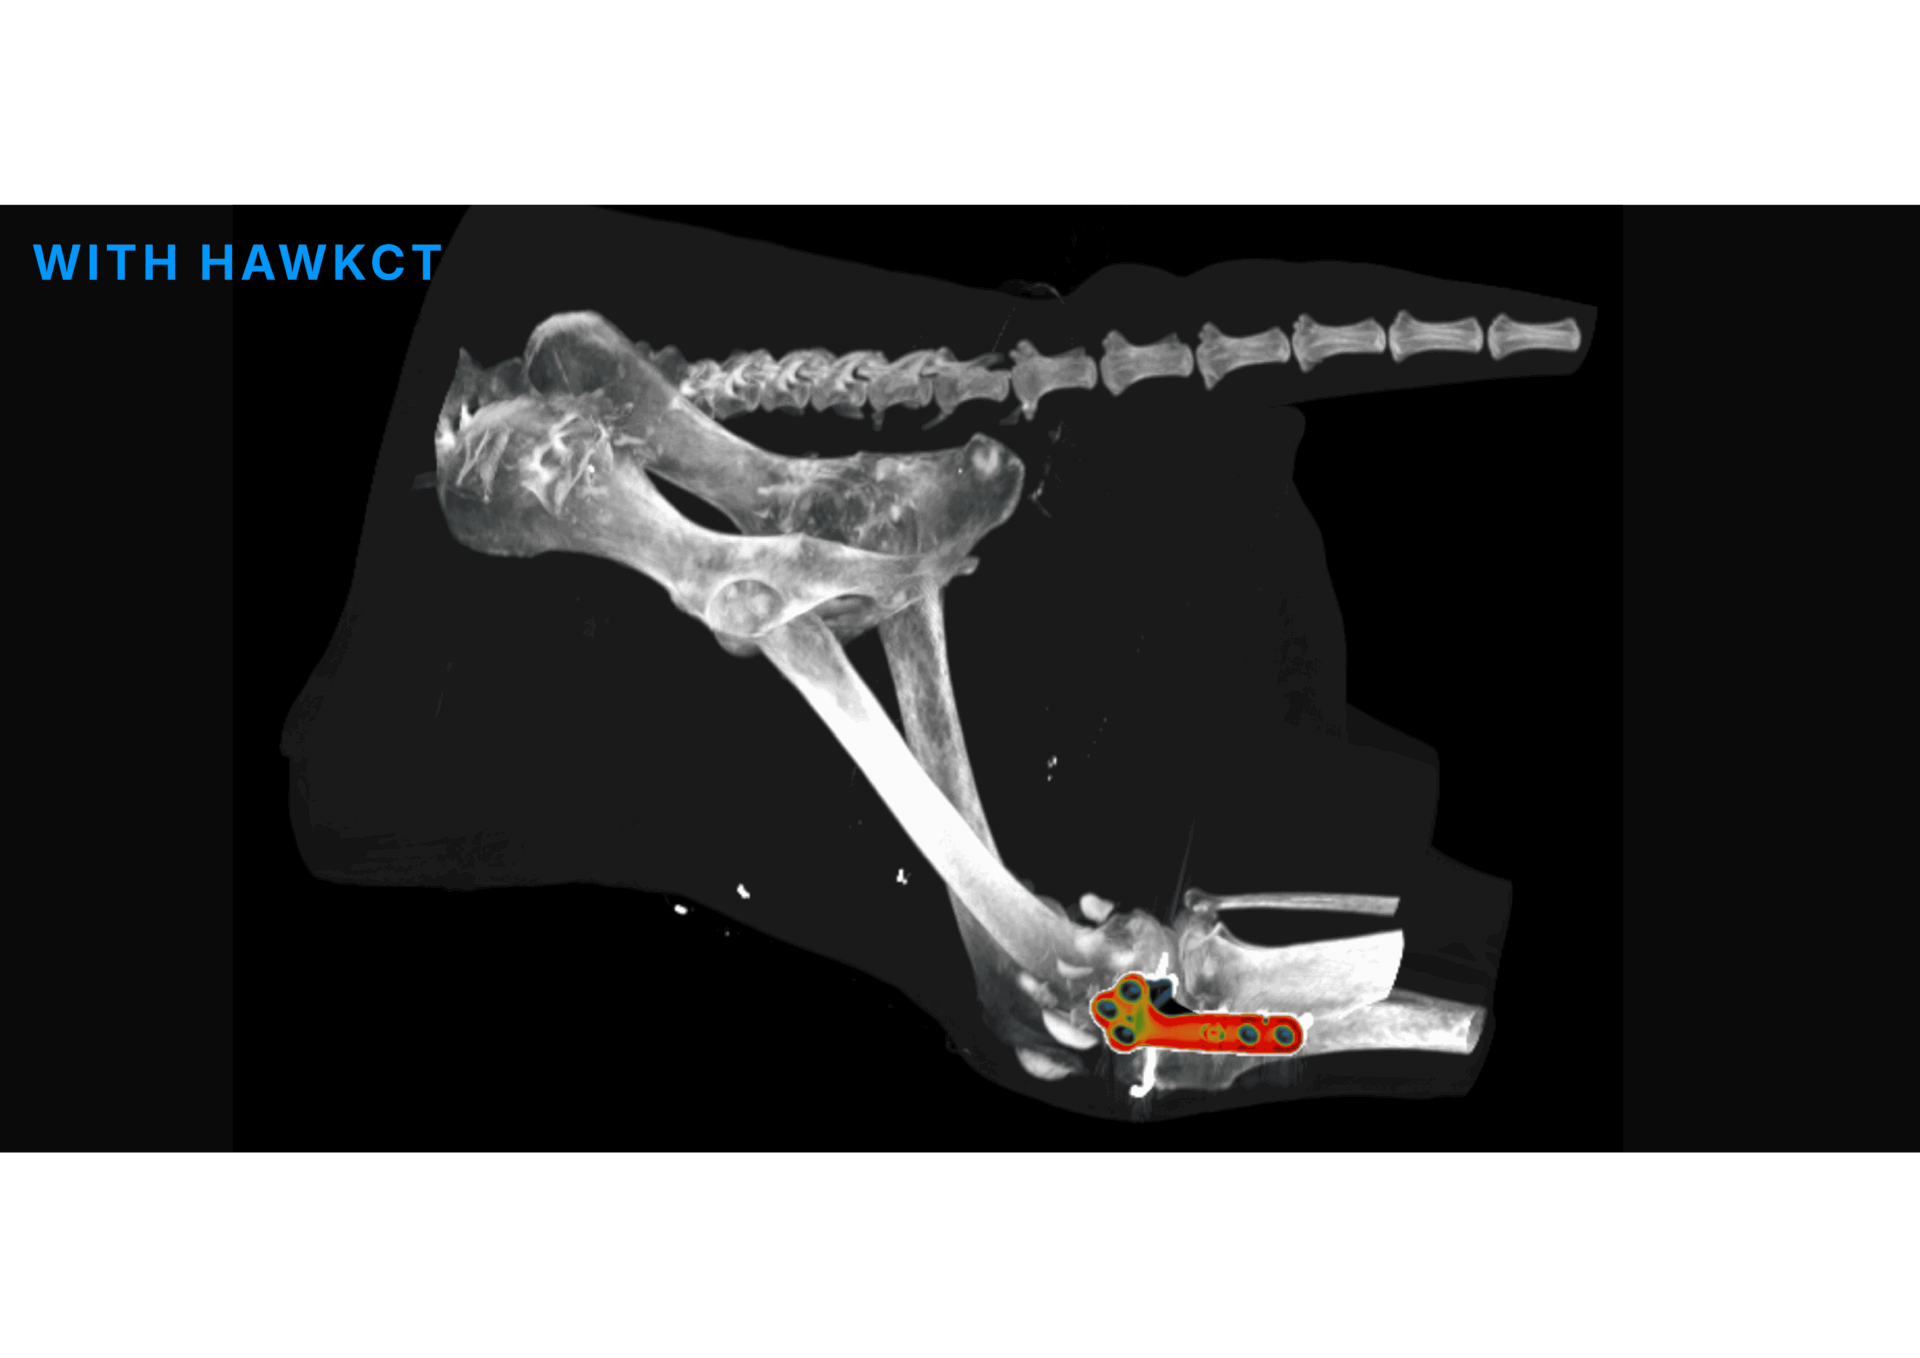

HawkCT is a veterinary CT deep learning algorithm designed to define a new standard in imaging. It delivers faster scans, reduced radiation exposure, and sharper image quality.

HawkCT optimizes workflows, lowers energy and consumable costs, and integrates seamlessly with any CT system. By cutting anesthesia time and reducing radiation dose, it improves patient safety while maintaining diagnostic precision. Its advanced reconstruction enhances contrast and resolution, providing consistent image quality across all sequences. Exclusively built for veterinarians, trained and validated on animal data, HawkCT empowers clinics with faster, safer, and more sustainable CT imaging.